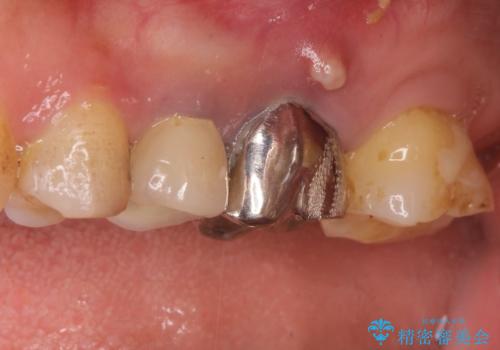

- 以前から奥歯に違和感があることを主訴に来院されました。歯肉にサイナストラクトを認めたため、再根管治療を行った後オールセラミッククラウンにて修復治療を行いました。根管治療は林先生に依頼しております。